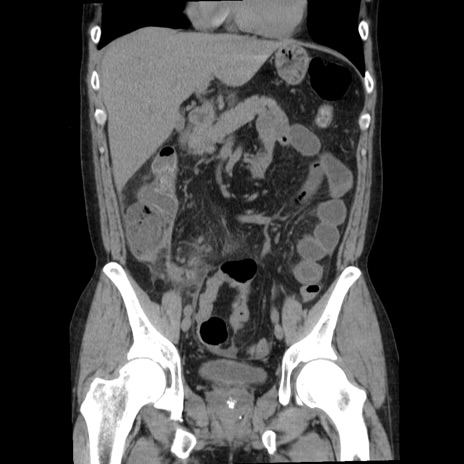

症例29(冠状断像)

【症例】40歳代男性

【現病歴】2日前から胃痛あり。徐々に周期的な激痛に変化した。本日になっても激痛があるため受診。

【身体所見】意識清明、BT 38-39℃台あり、腹部:膨満、やや硬、右下腹部に圧痛あり。

【データ】WBC 8500、CRP 23.26